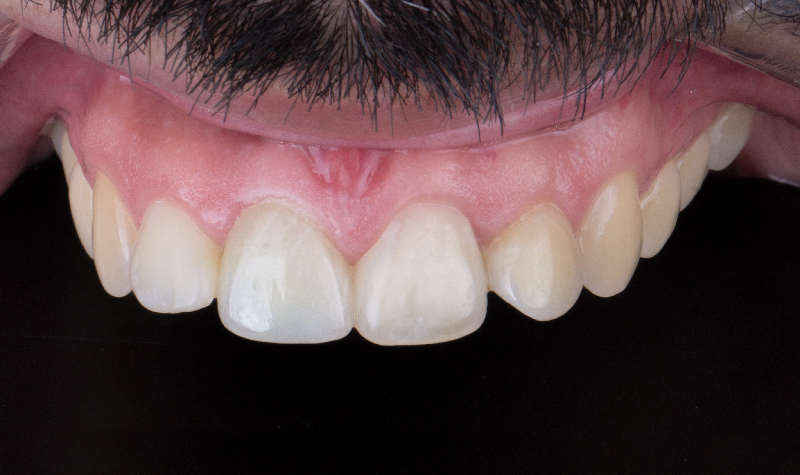

Prótesis híbrida inferior de cerámica fija sobre implantes.